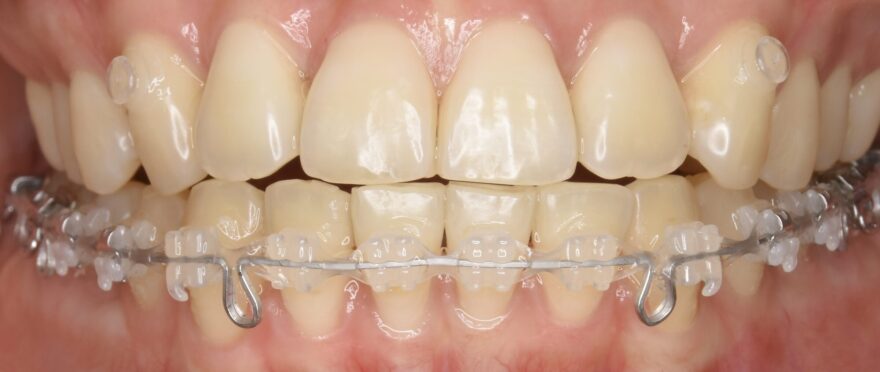

治療中の口腔内写真

上顎は裏側に矯正装置が付いています。

口蓋に2本の歯科矯正用アンカースクリューが埋め込まれ、裏側の矯正装置とゴムで繋がっていることがわかります。